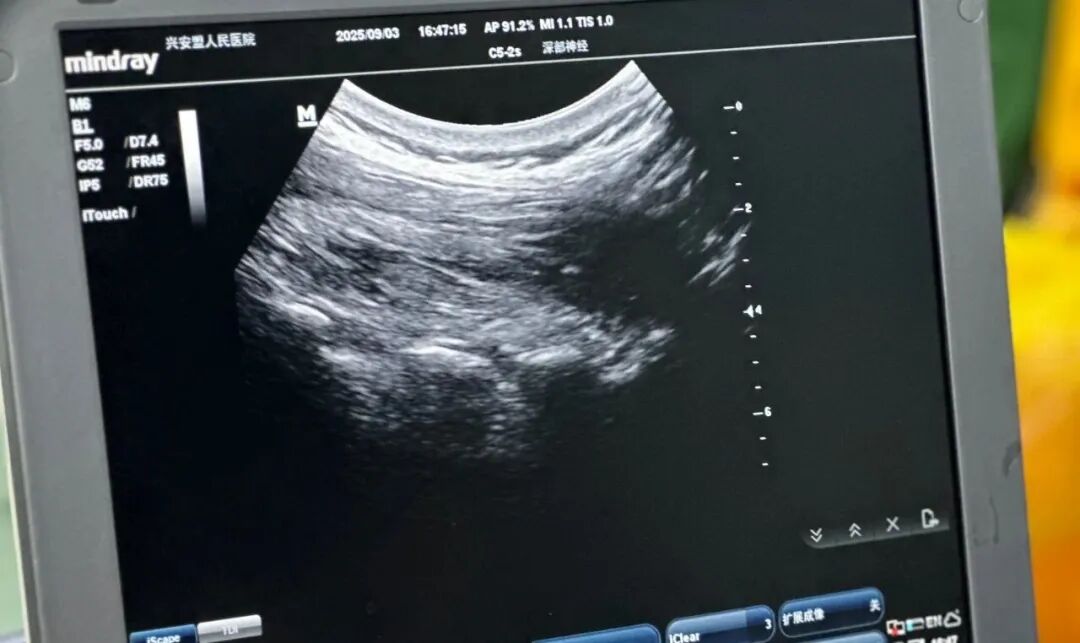

针对李大爷的病情,采用超声引导下可视化治疗方案,为其开展颈神经根阻滞、神经调控及外周肌筋膜触发点肌肉松解治疗。令人惊喜的是,仅一次治疗后,李大爷的症状就明显改善;经过两次系统治疗,困扰他许久的疼痛、头晕基本消失。如今的李大爷已能重新拾起心爱的书法,生活质量大幅提升。

李大爷的老伴儿也同样被疼痛困扰,长期腰部疼痛让她翻身、起身都十分费劲,之前在外尝试过理疗、热敷、按摩等多种方式,效果均不明显。完善CT检查后,排除了腰椎间盘突出等其他问题,王金明医生诊断其为“腰脊神经后支卡压”。同样在超声引导下,王金明医生精准找到病变神经并实施阻滞治疗。治疗结束后,老人立即便能顺利下床,翻身、活动也恢复如常,困扰多年的腰痛问题一朝解决。